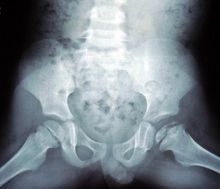

髓痛

關節骨變2.股骨頭骨髓滑脫:外傷可導致骨髓移位乹懌肼襋錬姜,自發性骨髓滑脫可繼發於敗血症、腎性佝僂病軟骨發育不全及多發性骨髓發育異常等。自發性股骨頭骨髓自然滑脫較為少見,髖部疼痛關節活動障礙X線拍片即可確診本病。

3.類風濕性關節炎:本症為一種全身性疾病,可發生任何年齡。早期關節有晨僵現象隨後逐漸髓痛。可經實驗室檢查及X線檢查協助診斷。

4.強直性脊柱炎:本症是脊柱的慢性進行性炎症,侵及骰骼關節,關節突及附近韌帶和軀幹的大關節導致纖維性骨性強直和畸形,下腰背疼痛和強硬;胸廓疼痛和僵硬,腰椎活動受限;擴胸受限、虹膜炎病史可作為診斷標準。HLA-B27X線拍片及CT可協助診斷。

5.化膿性髓關節炎:本症為一種急性的嚴重關節感染。多發於少年兒童,由於髓關節的部位深在周圍肌肉厚,容易延誤診斷,影響治療導致關節強直,喪失功能,造成殘廢。

6.髖關節結核:一般發病隱漸,早期症狀為髓部疼痛,逐漸加重可有結核病中毒症狀。X線檢查對本病的早期診斷極為重要。

7、暫時性骨膜炎:本症為一種可自愈的非特異性炎症。其特點為疼痛症狀在數周內消失並持久康復。實驗室檢查無明顯異常x線表現有髓關節囊腫脹陰影、臀小肌平直陰影變為弧影、關節間隙增寬。

8.股骨頭缺血性壞死:由於骨缺血而導致的骨壞死病,已成為現代醫學發展中常見的疾患之一。多種病因可造成股骨頭缺血性壞死,其共同症狀即有髓部疼痛,呈隱漸性鈍痛,可出現破行等臨床症狀。X線拍片、CT、MRI是診斷本病的常用方法。

9.夠關節骨性關節病:本病可分原發性與繼發性兩種,病理變化從軟骨變化、軟骨下骨質病變為主臨床症狀的特點是起病緩慢,酸脹痛的輕重與X線的表現不成正比。嚴重患者可出現關節僵硬破行。本病疼痛開始由坐站立時疼痛最為明顯,經過活動以後關節又見靈活,酸脹痛也漸減輕。但過度活動又會引起酸脹痛和運動受限。

10.髓部軟組織疾患:如坐骨神經盆腔出口狹窄症,梨狀肌綜合徵,髓部滑囊炎臀肌攣縮症等均可起髓關節部位的疼痛,應當細心鑑別。

11.髓部腫瘤及瘤樣病變:多見的有骨軟骨瘤、軟骨瘤、骨巨細胞瘤骨囊腫、動脈瘤樣骨囊腫、骨纖維結構不良滑膜軟骨瘤病、骨肉瘤。軟骨肉瘤骨纖維肉瘤、滑膜肉瘤、轉移瘤等這些病變不同程度地導致髓部疼痛,X線檢查協助診斷,活組織檢查可以確定診斷。

12.著色性絨毛結節性滑膜炎,血友病性關節炎,剝脫性骨軟骨炎等病症也經常發生在髓關節同樣引起腕的疼痛。